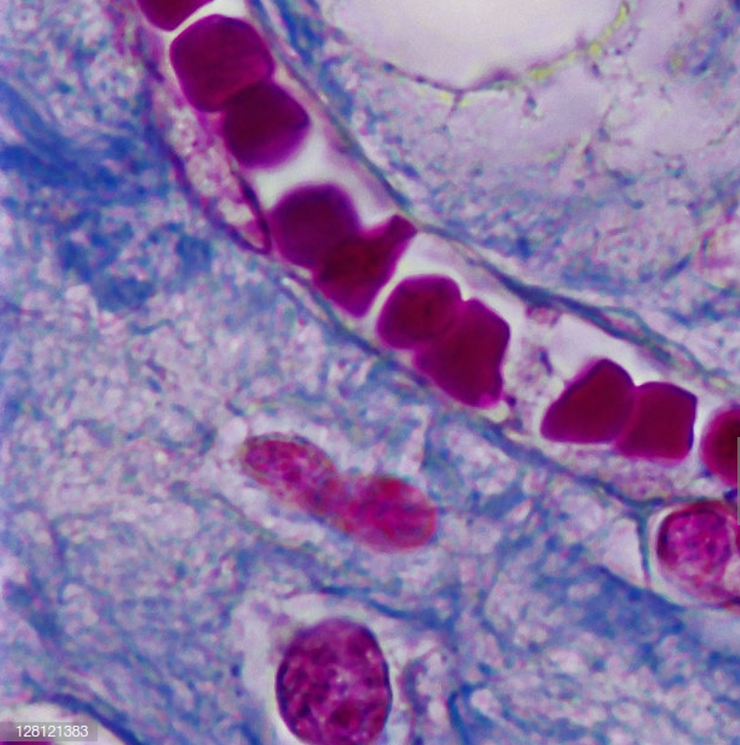

In order for the red blood cells to remove acidic metabolic waste and to pick up life giving oxygen they must pass through the pulmonary vein and then into the capillary pools. If the red blood cells are in pathological coagulation or aggregation there is no way to enter. Why? Because the entry into the capillary venules that branch off from the pulmonary vein measure 3 to 5 microns (1 micron is 1/25,000 of an inch – See Micrograph 1) and a single red blood cell measures 7 microns which makes it impossible for the red blood cell to enter the capillary venules if they are aggregated or coagulated into groups of red blood cells! [4]

When red blood cells group or clot together into a fibrin net, a clotting protein created when there is injury to the cell membrane and/or endothelial cells that protect the lining of blood vessels, (See Picture 2) the red blood cells cannot enter into the pulmonary vein and then into the capillary pools to release their acidic carbon dioxide waste and pick up oxygen in the alveolus of the lungs. (See Illustration 1)[5]

Pathological blood coagulation or disseminated intravascular blood coagulation (DIC) inside the pulmonary vein will prevent the free passage of red blood cells into the alveoli of the lungs via the pulmonary capillaries. {See Phase Contrast Micrograph 3 and 4) Erythrocytes or red blood cells must go into the pulmonary capillaries single file. If they cannot pass into the pulmonary capillaries of the lung to the alveoli this will cause oxygen deprivation that leads to red blood cell hypoxia (carbon dioxide poisoning) degeneration, genetic mutation, sepsis and sudden death.[6][7][8]